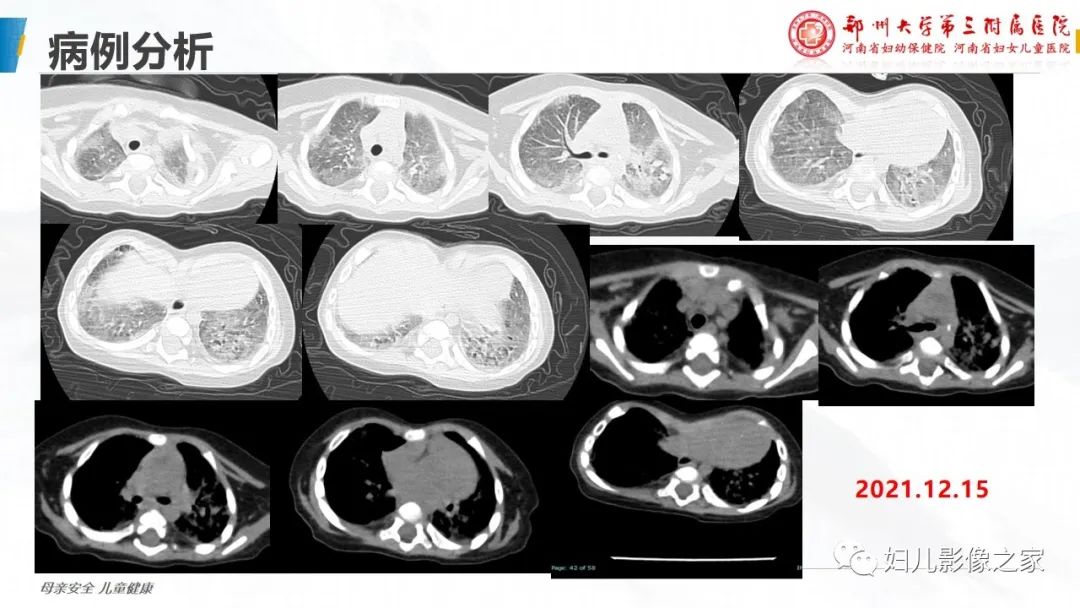

【PPT】肺泡蛋白沉积症的影像诊断-8